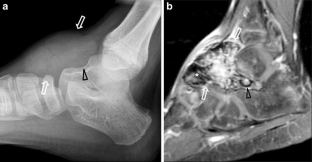

Fig. 2